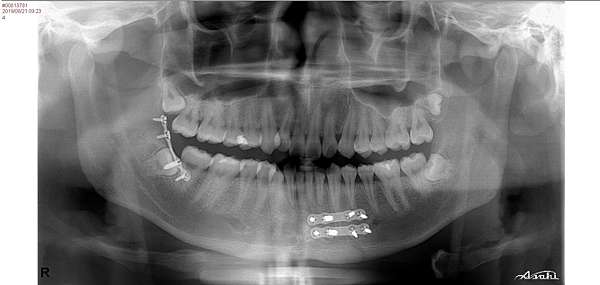

治療法 ほとんどの顔面骨骨折で緊急手術は必要ではなく、 1週間から10日以内に手術を行えば問題はありません。 下顎骨骨折では骨折の部位に応じて口の中や顎の下、耳の前などを切って開き、正しい咬み合わせが得られるように骨折した骨を戻した後

下顎骨骨折 治療方法-日口外傷誌 J Jpn Soc OMF Trauma 16:1424,17 原 著 小児下顎骨骨折の外科的治療 沖 田 美 千 子1) 針 谷 靖 史1) 関 口 隆1) 原 田 雅 史1) 石 戸 克 尚2) 1)医療法人渓仁会手稲渓仁会病院歯科口腔外科 (主任:関口 隆主任部長)下顎骨骨折の治療の目的は、たんに骨をひっつけることではなく、咬めるように治すことです。 すなわち正常咬合への回復が主眼となります。 有歯顎の場合は副子または歯牙結紮などを施し、 顎間固定 により骨片の整復と安静をはかります。